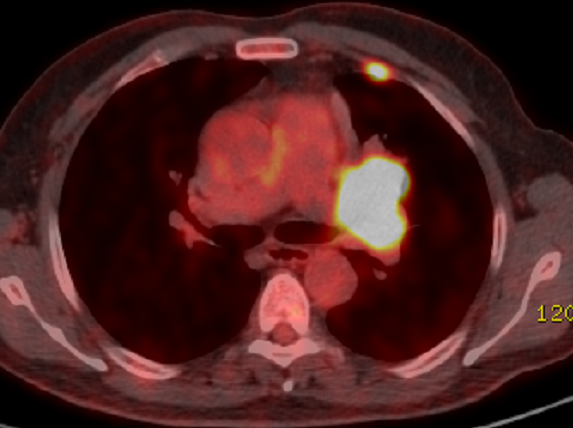

Akciğer kanseri ile akciğer tüberkülozunun (TB) aynı anda teşhis edilmesi nadir bir durum olmakla beraber, akciğer kanseri tanılı hastalar süreçleri boyunca immünsüpresif durumları (hastalığın seyri ve tedavi süreçlerine bağlı) ve ortak risk faktörlerinden dolayı tüberküloz açısından risk altındadırlar. Akciğer kanseri ile akciğer tüberkülozu arasında klinik ve radyolojik özelliklerin neredeyse her zaman benzer olması ise tanıyı geciktirebilmektedir. Bu nedenle akciğer kanserli olgularda TB’ dan şüphelenilen her durumda mikrobiyolojik testler cömertlikle kullanılmalıdır. Mikobakterium tüberkülozisin çevresindeki değişikliklerin algılaması ve bunlara yanıt vermesini sağlayan önemli bir düzenleyici olan tersinir protein fosforilasyonu, konakçıda hayatta kalması için gerekli dinamik adaptif yanıtların altında yatan ana sinyal mekanizmasıdır. Bu fosforilasyon serin/tirozin kinaz inhibitörleri ile sağlanmaktadır. Bu makalede tirozin kinaz inhibitörü olan afatinib tedavisi sırasında geniş spektrumlu antibiyotik tedavisine rağmen devam eden ateş ve öksürüğü sonrasında akciğer TB tanısı alan akciğer adenokarsinomlu olgu sunulmuştur. Although it is rare for lung cancer and pulmonary tuberculosis (TB) to be diagnosed at the same time, patients diagnosed with lung cancer are at risk for TB due to their immunosuppressive status (related to the course of the disease and treatment) and common risk factors. The fact that clinical and radiological features are almost always similar between lung cancer and pulmonary tuberculosis may delay the diagnosis. Therefore, microbiological tests should be used generously whenever TB is suspected in patients with lung cancer. Reversible protein phosphorylation, an important regulator that enables Mycobacterium tuberculosis to sense and respond to changes in its environment, is the main signalling mechanism underlying the dynamic adaptive responses required for host survival. This phosphorylation is provided by serine/tyrosine kinase inhibitors. In this article, we report a case with lung adenocarcinoma diagnosed as pulmonary TB after persistent fever and cough despite broad-spectrum antibiotic treatment during afatinib treatment, a tyrosine kinase inhibitor.